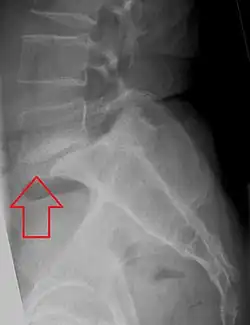

X-ray of measurement of spondylolisthesis at the lumbosacral joint, being 25% (grade 1) in this example -

X-ray picture of a grade 1 isthmic anterolisthesis at L4-5 -

MRI of L5-S1 anterolisthesis -

X-ray of a grade 4 anterolisthesis at L5-S1 with spinal misalignment indicated